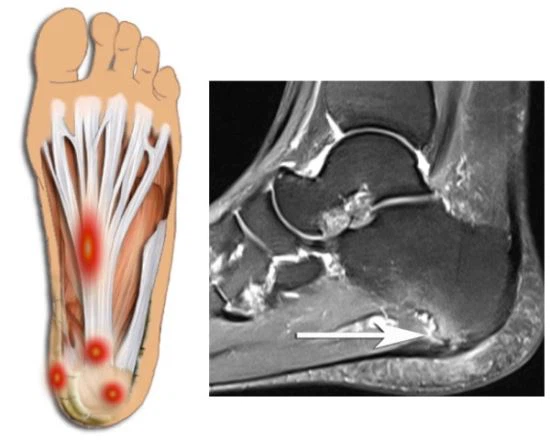

족저 근막염 증상 중 대표적인은 것은 오전에 일어나 처음 발을 내디딜 경우 느껴지는 심각한 진통이 특징입니다. 진통은 대부분 발뒤꿈치 안쪽에서 유발생하는 경우가 많습니다. 오전에 일어나서 발생하는 진통의 경우 수면 중 경직된 족저근막이 늘어나면서 발생하는 것으로 알려져 있습니다.

족저근막에 이상이 발생하면 발뒤꿈치에 진통이 나타납니다. 진통이 내부 깊숙한 곳으로부터 나타나는데, 증상이 심할 때는 발 전체가 아파 서있기도 힘듭니다.

또한 오전에 몇 걸음 걸을 경우 수면 중 경직되어있던 족저근막이 펴지며 심각한 통증을 느끼게 되는데, 자는사이 이용하지 않던 발이 땅바닥에 닿으며 통증이 느껴지게 됩니다.